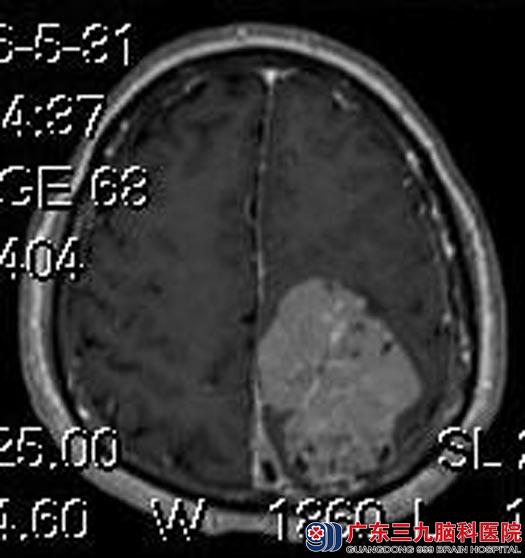

黄先生一个月前出现右侧肢体麻木, 一天前感觉右侧肢体麻木较之前加重,伴有阵发性头痛、呕吐,当地人民医院头颅CT示“左顶镰窦脑膜瘤”。头颅MR检查提示:左侧顶部镰窦旁巨大脑膜瘤,大小约6.11cm×4.78cm×5.59cm;MRV提示:顶部上矢状窦局部未显影,考虑肿瘤压迫所致。头颅CTA提示:左顶部镰窦旁巨大占位病变,其内多大细小供血血管,呈反射状分支,来源脑膜动脉可能性大。

由综合神经外科鲁明主任主刀,在全麻下行左侧顶部大脑镰窦巨大脑膜瘤切除+上矢状窦修补+颅内压探头置入术,术中显微镜下见灰白色肿瘤,质中偏硬,血供丰富,先电灼、沿矢状窦分离肿瘤基底部,再分块分离切除肿瘤。包膜完整,大小约6cm×5cm。见肿瘤侵入窦内,切除窦内残留肿瘤,修补上矢状窦,术中出血约800ml,输红细胞悬液2U。术后黄先生肢体活动正常,病理结果:过渡型脑膜瘤(WHO I级)。